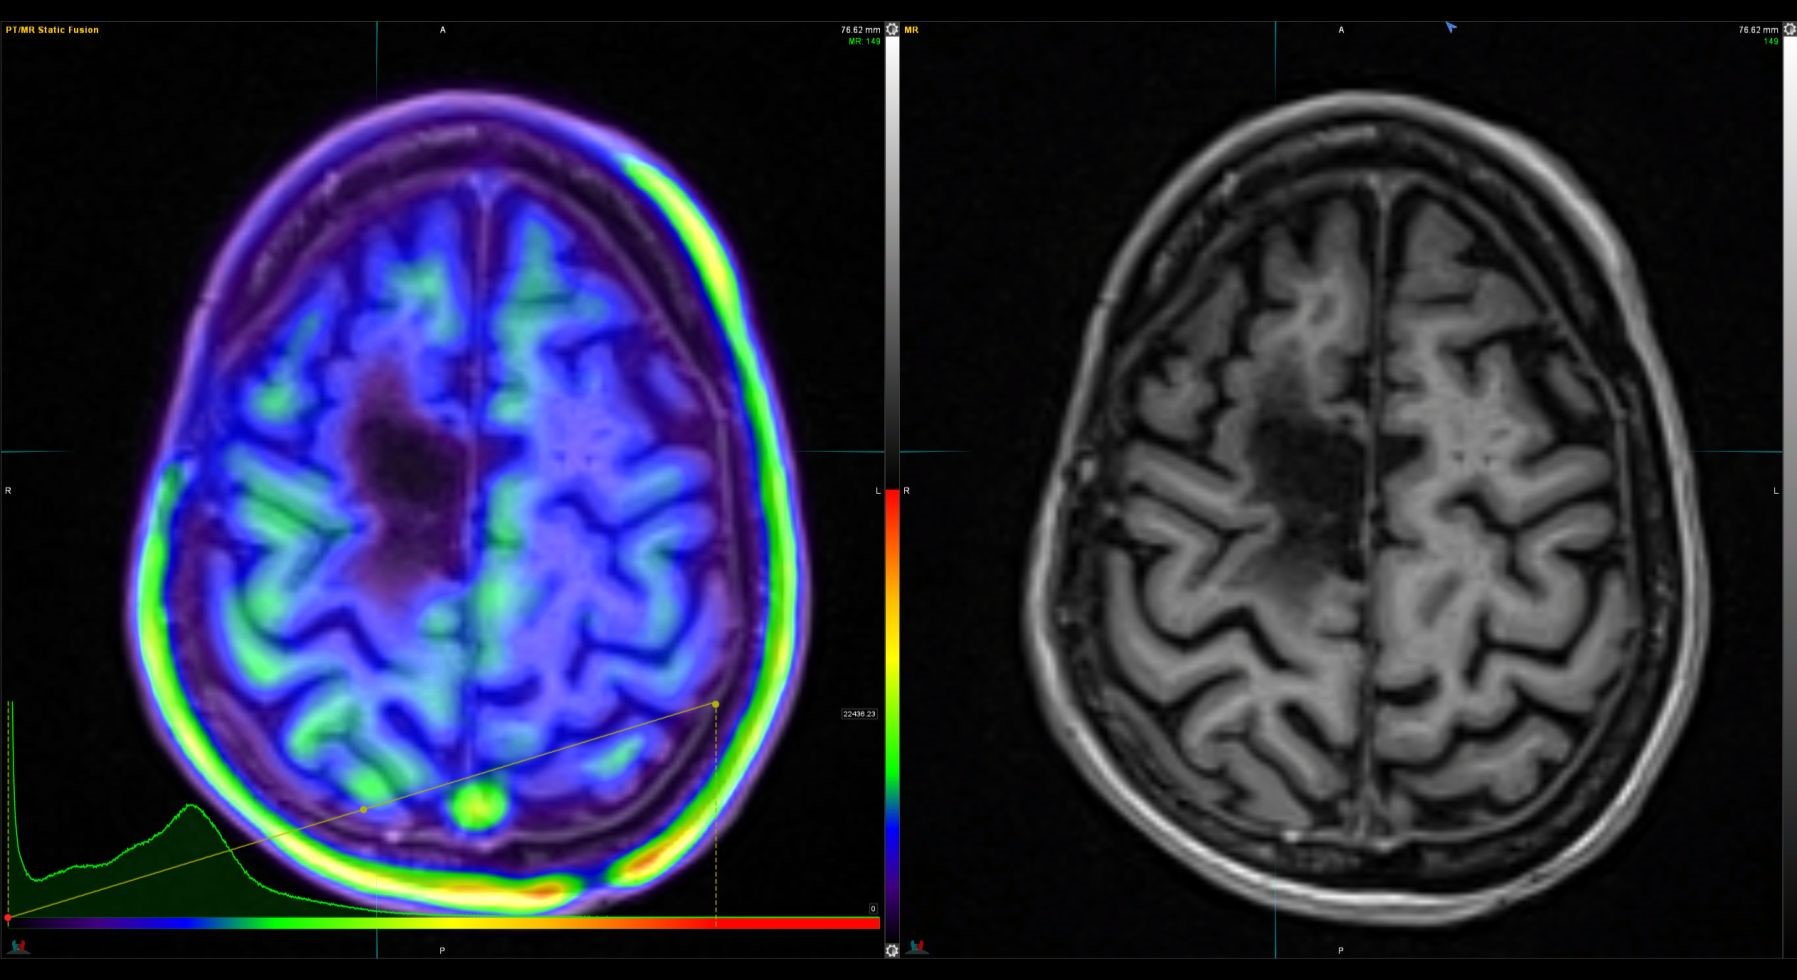

Η Τομογραφία Εκπομπής Ποζιτρονίων (PET) αποτελεί μια εξειδικευμένη μέθοδο της Πυρηνικής Ιατρικής που χρησιμοποιεί μοριακή απεικόνιση για να εντοπίσει και να παρακολουθήσει φυσιολογικές και παθολογικές λειτουργίες του οργανισμού. Συνδυάζοντας τη λειτουργική απεικόνιση της PET με την ανατομική πληροφορία της αξονικής τομογραφίας (CT), η υβριδική εξέταση PET/CT παρέχει εικόνες υψηλής ευκρίνειας και τη δυνατότητα ποσοτικής αξιολόγησης των βιολογικών μηχανισμών σε κυτταρικό επίπεδο.

Η PET/CT αποτελεί εξαιρετικά προηγμένη τεχνική της σύγχρονης ιατρικής απεικόνισης και χρησιμοποιείται τόσο για τη διάγνωση όσο και για την παρακολούθηση της ανταπόκρισης στη θεραπεία.

Οι κυριότερες εφαρμογές της αφορούν την ογκολογία, τη νευρολογία και, σε μικρότερο βαθμό, την καρδιολογία, ενώ συνεχώς αναπτύσσονται νέες χρήσεις σε άλλες ιατρικές ειδικότητες.

Με τη χρήση ειδικού λογισμικού Τεχνητής Νοημοσύνης (MIM – Lesion ID) πραγματοποιείται αυτόματος υπολογισμός της έκτασης και του όγκου των θέσεων ενεργού νόσου. Ξεπερνώντας τις δυνατότητες του ανθρώπινου οφθαλμού υπολογίζεται το συνολικό φορτίο νόσου πριν και μετά την θεραπεία επιτρέποντας ακριβέστερο χειρισμό του ασθενούς από τον θεράποντα ιατρό.

Στο Κέντρο PET/CT πραγματοποιούνται εξειδικευμένες εξετάσεις που καλύπτουν ένα ευρύ φάσμα κλινικών εφαρμογών στη σύγχρονη Πυρηνική Ιατρική. Ανάλογα με το είδος του προβλήματος και τη φύση της νόσου, χρησιμοποιούνται διαφορετικά ραδιοφάρμακα για τη μελέτη συγκεκριμένων βιολογικών μηχανισμών.